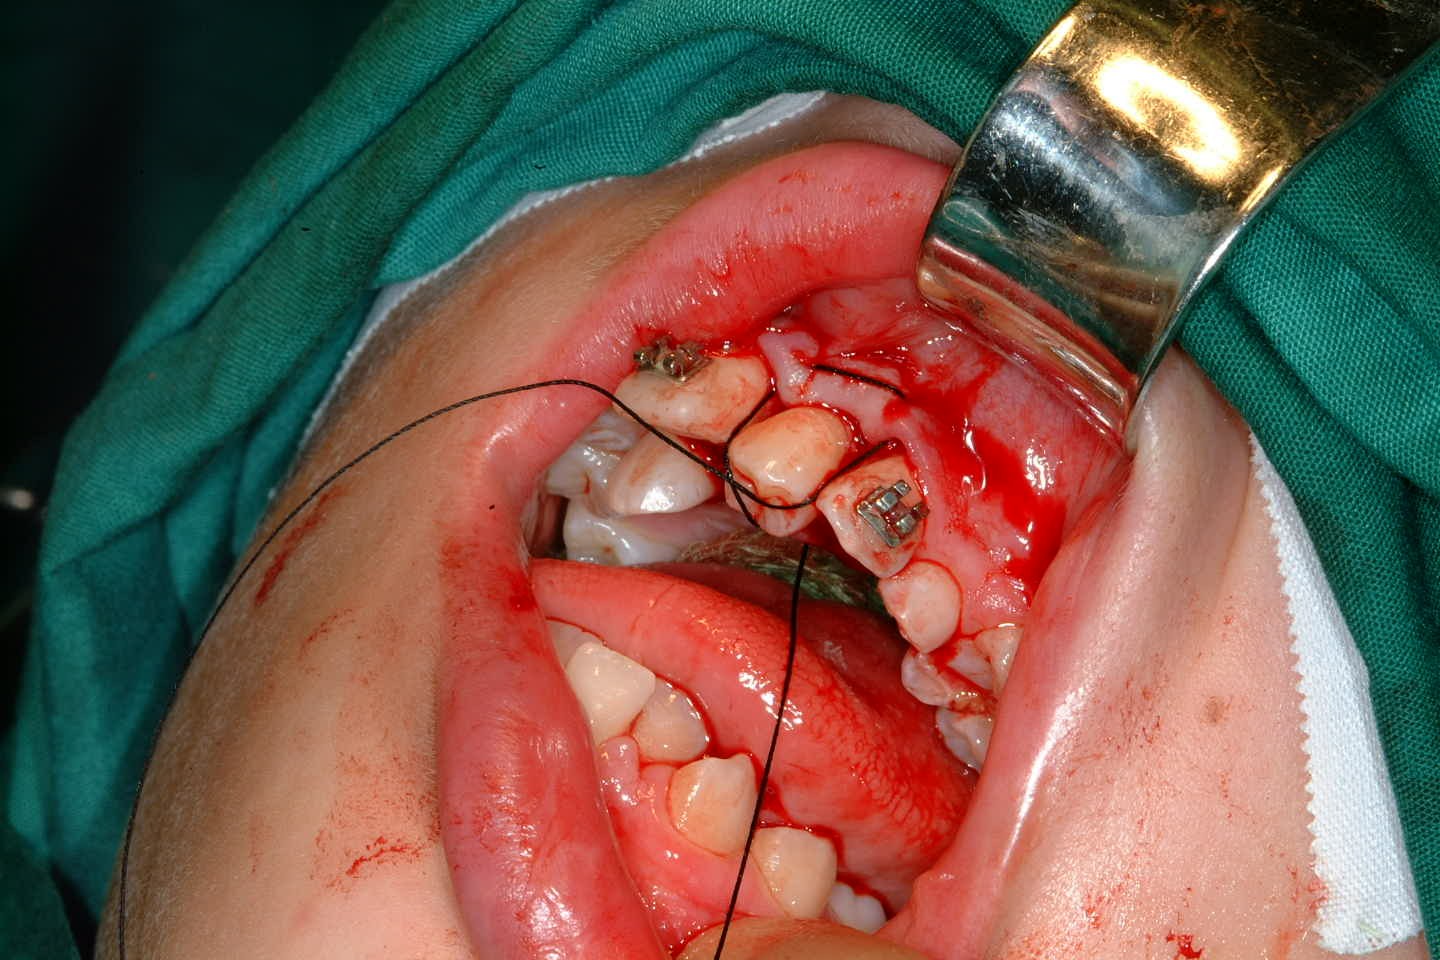

Once the tooth has been transplanted it should be splinted for between 7 and 14 days. This may be with a preformed splint cemented with a luting material or even with appropriately placed sutures (Figure 24). The area should not be disturbed during the healing phase to allow optimal healing of the periodontal ligament.